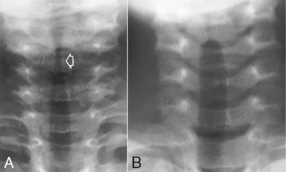

T7 for the PA chest can be located posteriorly in reference to C7, the vertebra prominens. Level of T7 is 7-8 inches (18-20 cm) below the vertebra prominens.

The CR for the AP chest is 3-4 inches (8-11cm) below the jugular notch and angled 3°–5° caudad.

• Center CR to T7 region. Top of IR will be approximately 2″ (5 cm) above shoulders on average patient.

CR ⊥, to midthorax at level of T7. Generally IR and CR should be lowered ≈1″ (2.5 cm) from PA on average patient.